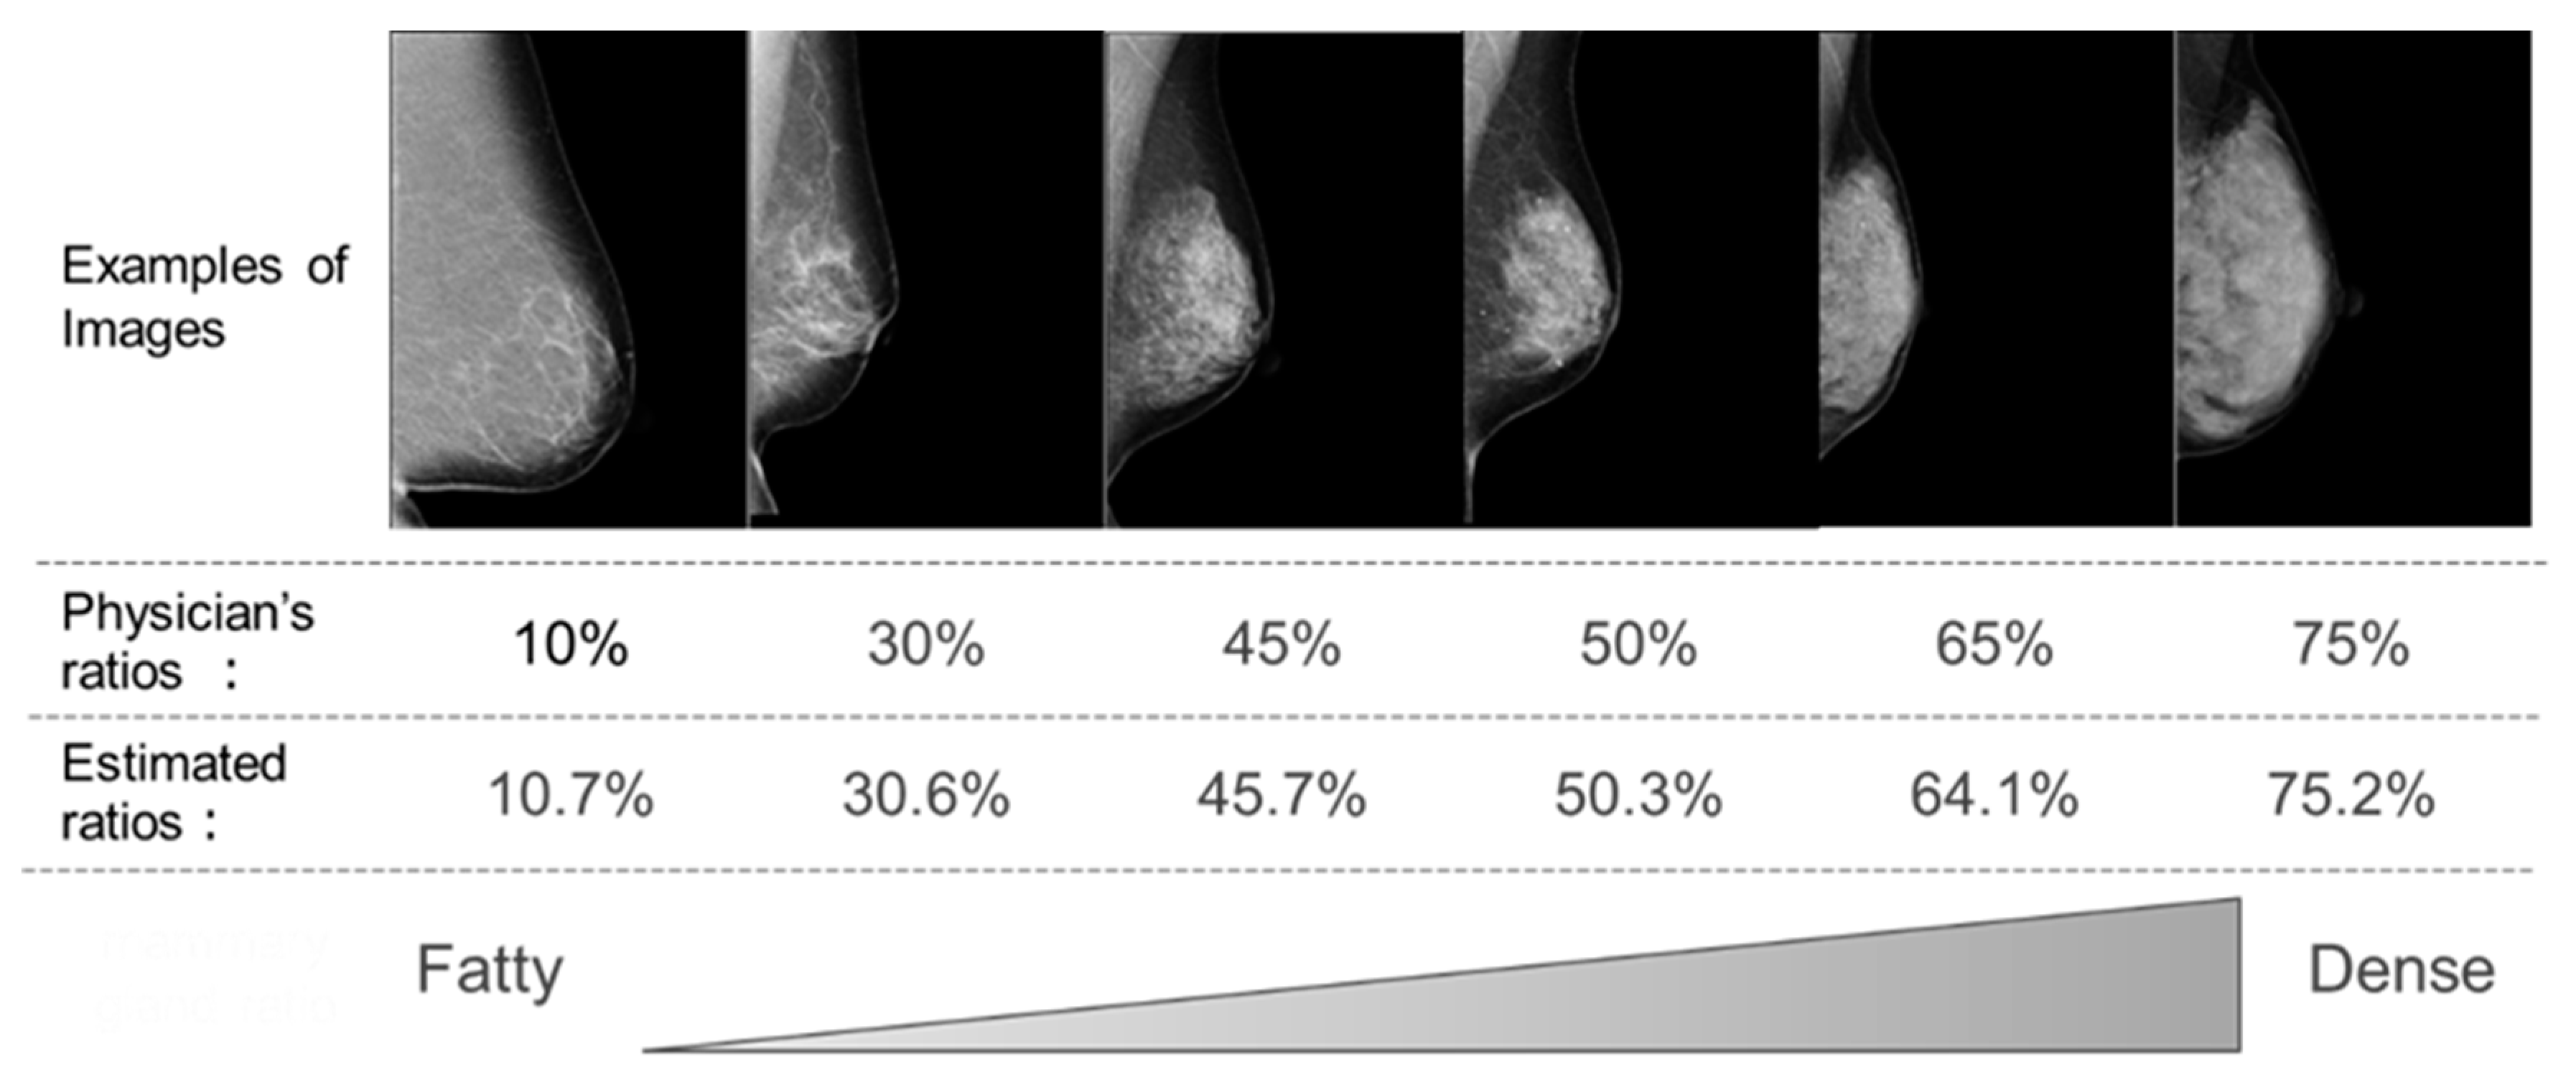

2. Materials and Methods

3. Results